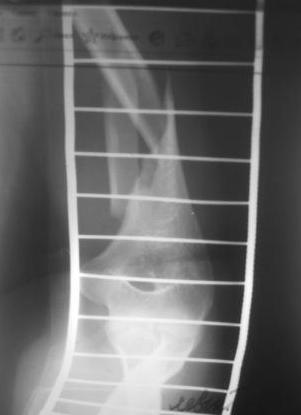

Уважаемый товарисч.Данный перелом можно вылечить антероградным, ретроградным штифтованием, пластиной, аппаратом внешней фиксации, вытяжением за локтевой отросток на шине ЦИТО. Учитывая наличие тяжелой ЧМТ предпочтение должно отдаваться минимальноинвазивной технике.

Качество паредставленных Вами рентгеновских снимков крайне низкое, что косвенно свидетельствует об общей культуре работы в Вашем отделении.

Humerus.jpg